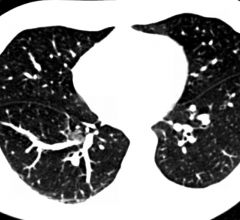

Previous evidence, including published National Lung Cancer Screening Trial (NLST) results, shows that computed tomography (CT) lung cancer screening significantly reduces lung cancer deaths in high risk patients*, and is appropriate, with careful patient selection and follow-up. This benefit significantly outweighs the comparatively modest rate of overdiagnosis noted in an article published online Dec. 9 in JAMA Internal Medicine. The American College of Radiology (ACR) will continue guideline and appropriateness criteria creation to support CT lung cancer screening programs across the country.

The American College of Radiology (ACR) and the Radiological Society of North America (RSNA) joined more than 100 medical societies in 57 countries around the world in celebrating the second annual International Day of Radiology (IDoR) on Nov. 8. IDoR 2013 focused on the important role lung imaging plays in the diagnosis and treatment of lung diseases, including the advent of computed tomography (CT) lung cancer screening.

Americans at increased odds of a potentially lethal lung cancer diagnosis may soon be able to seek out the most promising technology available to detect it early and ultimately have screening covered by insurance, including Medicare. The U.S. Preventive Services Task Force (USPSTF) recommended a high "B" rating for annual computed tomography (CT) scans for current and former smokers, aged 55 to 80, with a history of heavy smoking (two packs per day over 20 years or one pack a day over 30 years).